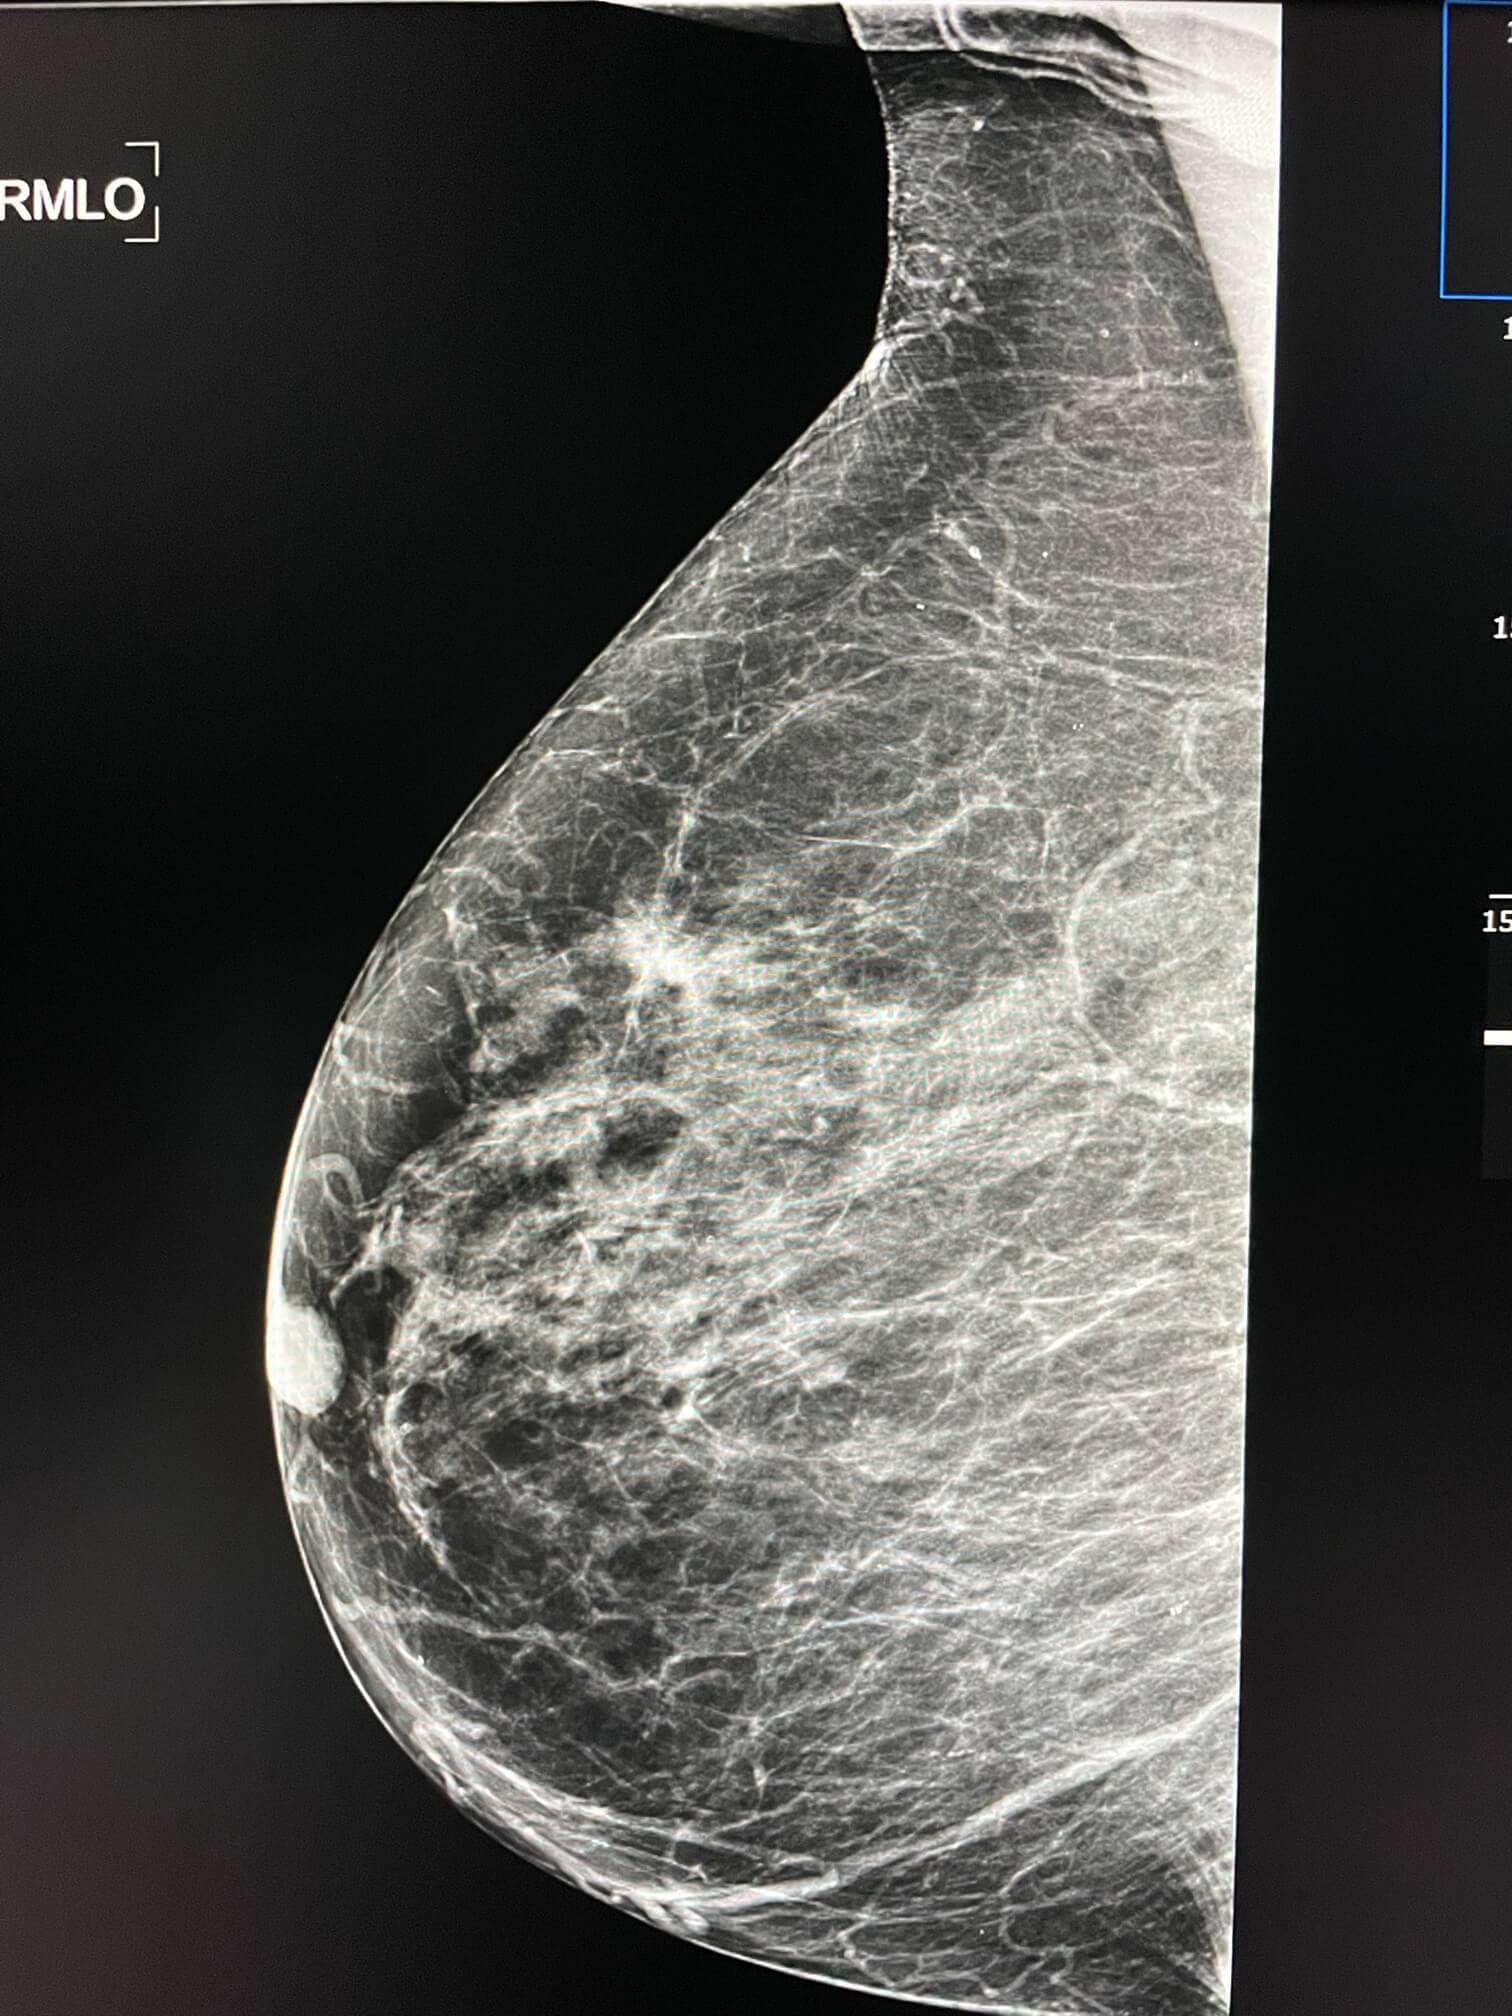

75-year-old female. Increase in opacity detected in screening mammogram.

A first mammogram in December 2020 showed an increase in opacity pointed out by Mammoscreen in the right breast, a first radiologist performed an ultrasound without any suspicious abnormality.

Mammoscreen again points to the same extra density of the right breast.

However, the extra opacity does not disappear on the compression slice.

Mammoscreen confirms the suspicion of the radiologist, who completed with an MRI that confirms a suspicious lesion at the union of the upper quadrant of the right breast.